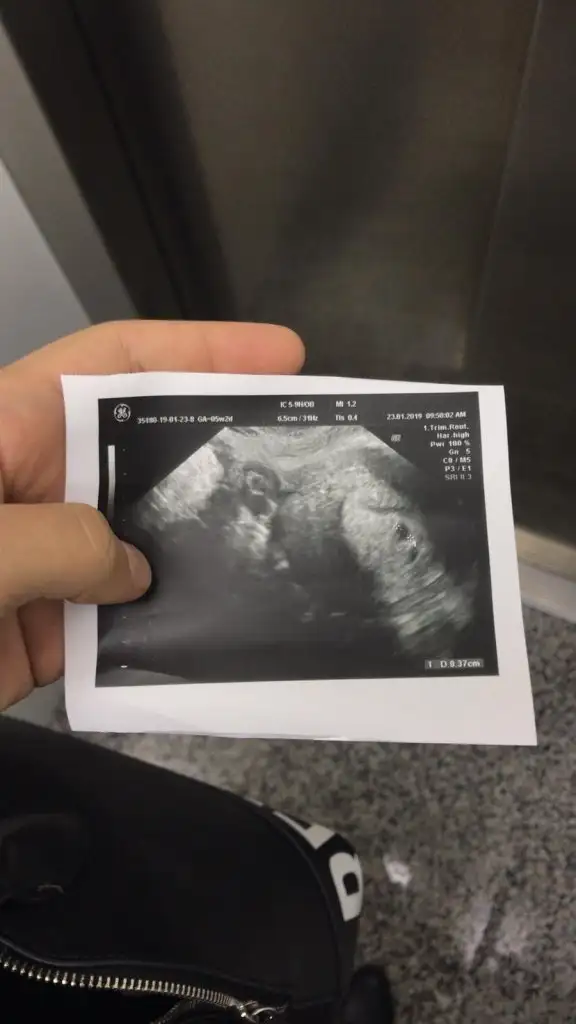

Bak buldum eski ultrasonumdan benimde vajinaldiVajinalde küçük gördüler zaten normalde vajinalde daha büyük olmasını bekleriz dediler

Sizin de 3,7 mm imiş evet hadi hayırlısı çok rahatladım yazılanlarla herkesten Allah razı olsjnBak buldum eski ultrasonumdan benimde vajinaldi